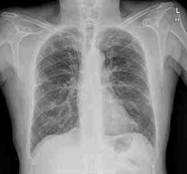

Enfermedad Pulmonar

Obstructiva Crónica (EPOC) es un desorden respiratorio crónico que comprende

a la bronquitis crónica y al enfisema pulmonar, y está caracterizado por

exacerbaciones definidas como: